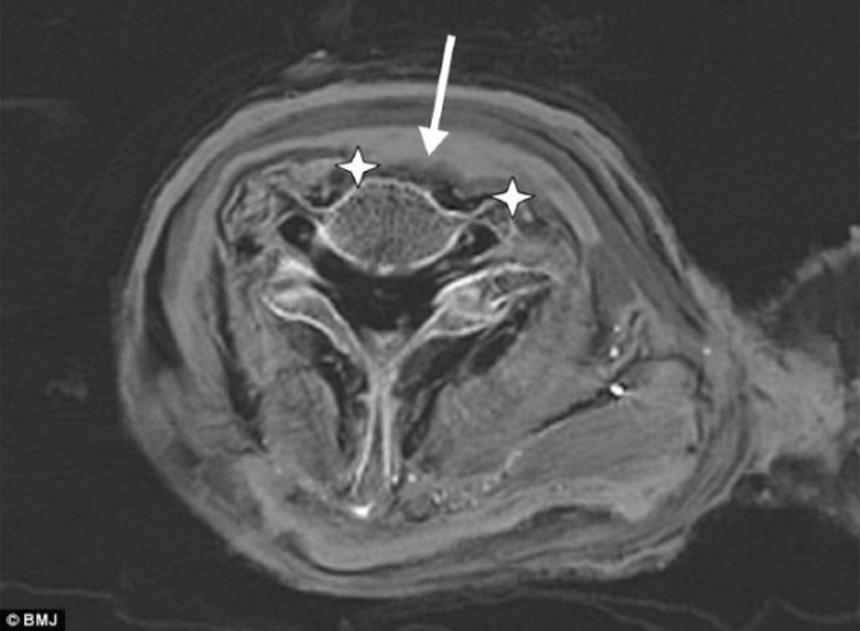

ラムセス3世のミイラのCT画像によると、王の気管と主幹動脈は裂けており、傷は左右7センチにわたり、深さは脊椎にまでほぼ達していたことが分かった。またこの傷によって、首の前面部の軟組織は完全に傷んでいた。

ラムセス3世のミイラ CT画像

この画像を大きなサイズで見るイタリアにあるボルツァーノ欧州アカデミー内の「ミイラとアイスマン研究所)」の古病理学者、アルバート・ジンク氏は「首にあるこの切り傷によりラムセス3世は殺されたという事実にほぼ疑いはない。傷は非常に深く極めて大きく、骨(脊椎)にまで達している。致命傷だったことは間違いない」と述べている。

喉をかき切られたのは死んでからだった可能性もあるが、古代エジプトのミイラ作成技術にはそうした方法はまったく記録されていないことから、その可能性は非常に少ないと研究チームは述べている。